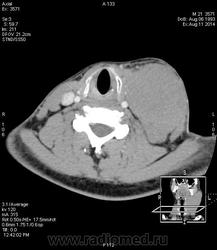

Наблюдение Tatarin

Пролимфоцитарная лимфосаркома высокой степени злокачественноститипа Беркитта.

Еще одна печальная история. "Ужас" нашего городка. (как в передаче Городок) Парень 21 г. Со слов матери в мае '14 года на шее слева образовалась небольшая "шишечка", в поликлинике посмотрели и отправили к хирургу в стационар. С 15.05 по 27.05 находился в  отделении гнойной хирургии с Ds: Острый гнойный шейный лимфаденит слева. В общем хирурги решили удалить лимфоузел, удалили да не весь, гистологи написали что не могут оценить структуру. Удалили да удалили, ах да еще физио назначили, магнитные поля для улучшения микроциркуляции, все дела, только как сказала мать пациента "шишечка" стала "расти как на дрожжах". В итоге пациента выписывают, со словами "мы ничего не можем сделать", сказав матери " мы лечили гнойный лимфаденит, но это не он." crying Оторвать бы им руки... Обратились к знакомому онкологу, взяли биопсию.

Вот такая стремительная динамика...15.05 "шишечка", а дальше-больше, особенно после "лечения" и физиотерапии.

КТ 11.06.14

КТ  11.08.14 (через 2 месяца) после двух курсов ПХТ, перед третьим...растет...